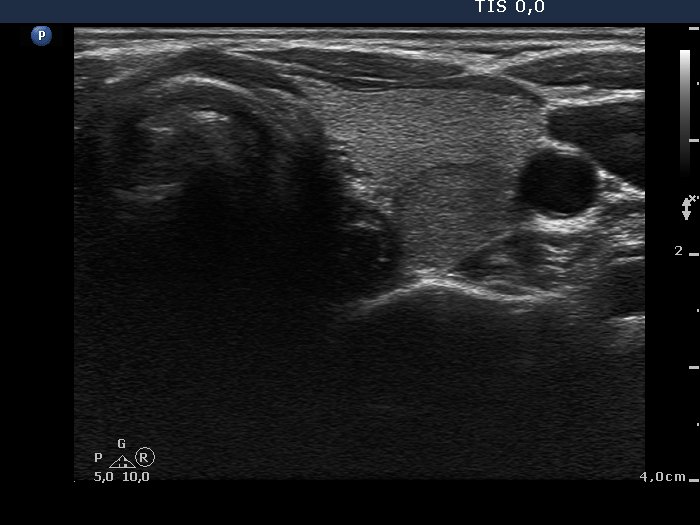

100 consecutive cases of papillary cancer - case 001 (ultrasonographic picture 7)

Lower part of the left lobe, transverse scan. There is a moderately hypoechogenic nodule in the dorsal part.